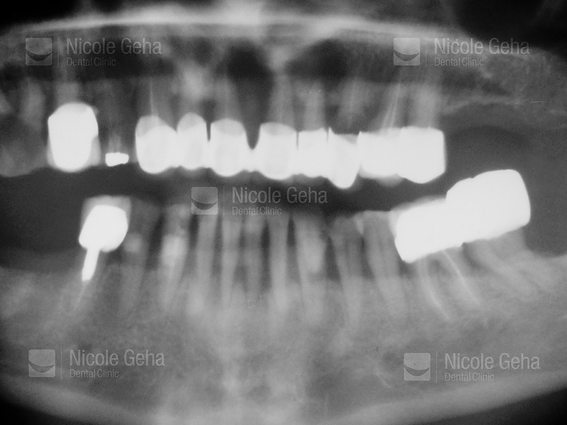

FULL MOUTH

case 1: before

case 1: after